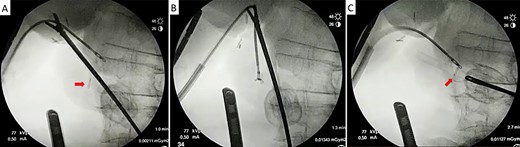

The metallic clip is recognized enclosed in biliary sludge. Notice that the clip is closed but both branches cross, denoting an incorrect closure.